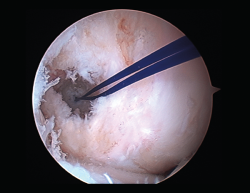

Figura 7. Adherencias intraarticulares.

Las principales causas secundarias a errores técnicos son la malposición de la plastia y el tensado excesivo. La radiografía permite ver la localización de los túneles e implantes, así como la RM visualiza las partes blandas implicadas, pudiendo identificar posibles pinzamientos de la plastia –escotadura intercondílea, síndrome del cíclope (Figura 9), síndrome de la contractura infrapatelar(22)(Figura 10)–.